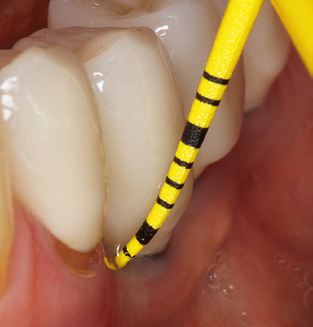

L'attuale piano di lavoro per SPT

L'aggiornamento della storia medica del paziente è un aspetto importante di SPT e dovrebbe avvenire almeno una volta all'anno. Aiuta il team dentale a identificare e documentare eventuali nuovi fattori di rischio. Soprattutto quando un paziente viene curato per molti anni, è importante stabilire se i fattori di rischio per la salute specifici del paziente e generali sono cambiati. Ciò riguarda principalmente un aumento del rischio a causa del diabete, ma altre condizioni generali (malattie cardiovascolari e neoplasia) possono anche produrre un profilo di rischio modificato a seguito del trattamento eseguito e della somministrazione dei farmaci. Di conseguenza, l'aggiornamento della storia medica come parte di SPT è molto importante, poiché un profilo di rischio modificato può innescare la necessità di adattare l'intervallo di trattamento. Nel passaggio successivo, è importante prestare la dovuta attenzione alla diagnostica. Mentre gli strumenti sono un aspetto centrale di SPT, i risultati e la loro documentazione non devono mai essere trascurati. I risultati parodontologici sono essenziali per una buona diagnosi; aumenti della profondità della tasca e l'indice BOP sono chiari indicatori dell'avanzamento della malattia parodontale e perimplantare. Pertanto, il team non dovrebbe evitare di sondare anche gli impianti, con l'obiettivo di raccogliere i dati richiesti. Allo stesso tempo, è importante utilizzare sonde parodontali con segni millimetrici. Le sonde metalliche sono già state utilizzate per determinare la profondità della tasca attorno ai denti naturali per decenni. Nel caso degli impianti, la sfida di registrare profondità delle tasche corrette e riproducibili è ancora maggiore. Poiché la discrepanza tra il diametro dell'impianto e il contorno della sovrastruttura si traduce regolarmente in un over-contouring della sovrastruttura, le sonde flessibili che presentano ancora marcature millimetriche sono una soluzione sensata per misurare la profondità della tasca attorno agli impianti (ad es. Colorvue Kit PCV11KIT6, HuFriedy; Fig. 4 ).